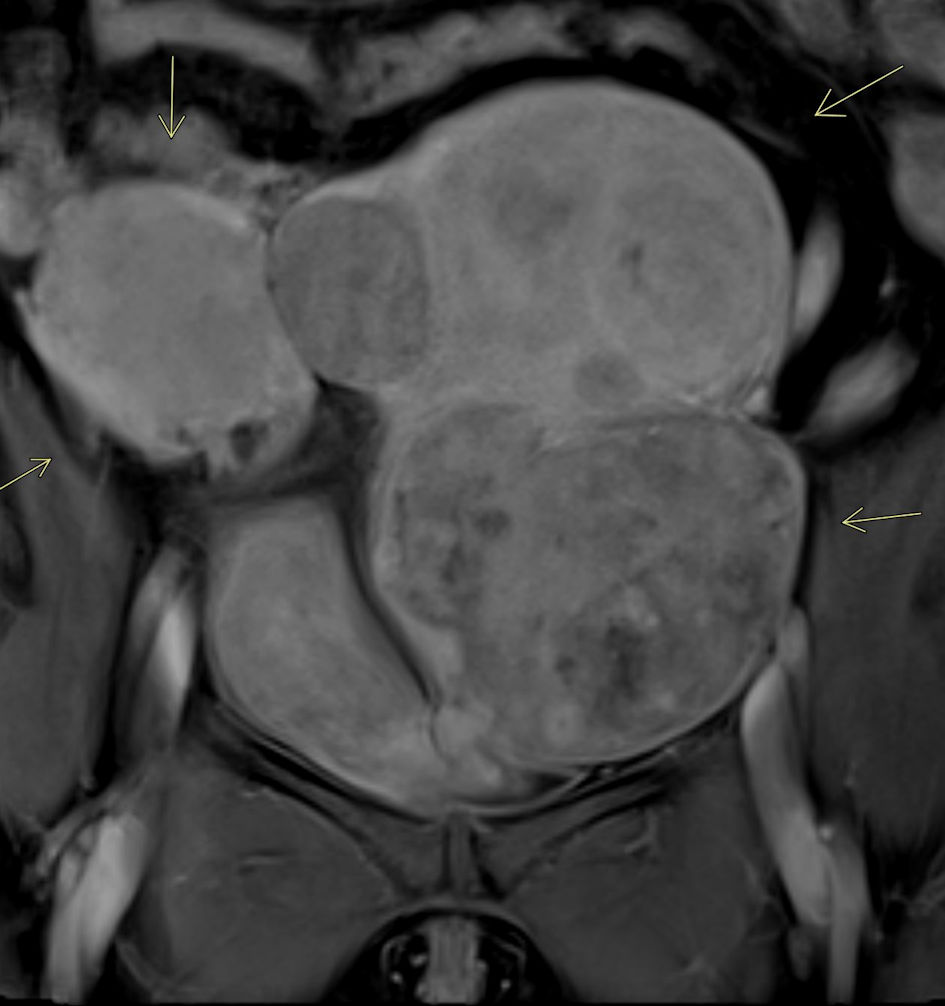

A magnetic resonance imaging (MRI) was subsequently ordered to further evaluate the extent of her uterine fibroids and anatomical variation due to uterine didelphys. MRI confirmed the presence of uterine didelphys with multiple large enhancing uterine fibroids distorting the endometrial cavity (Fig. 1). Fibroids were identified in both uteri, with the largest on the left measuring 14 × 11 × 11 cm and the largest on the right measuring 5.8 × 5.5 × 4.7 cm. Magnetic resonance angiography (MRA) demonstrated normal pelvic arterial anatomy with bilaterally enlarged uterine arteries, more prominent on the left. Prior to uterine artery fibroid embolization, MRA provides excellent visualization of the pelvic anatomy, assisting the interventionist in pre-procedural planning for the procedure (Fig. 2).

Figure 2. MRA of pelvis. Pelvic MRA confirms the highly vascular nature of the uterine fibroids, particularly notable in this case involving multiple large fibroids affecting both uteri (arrows).